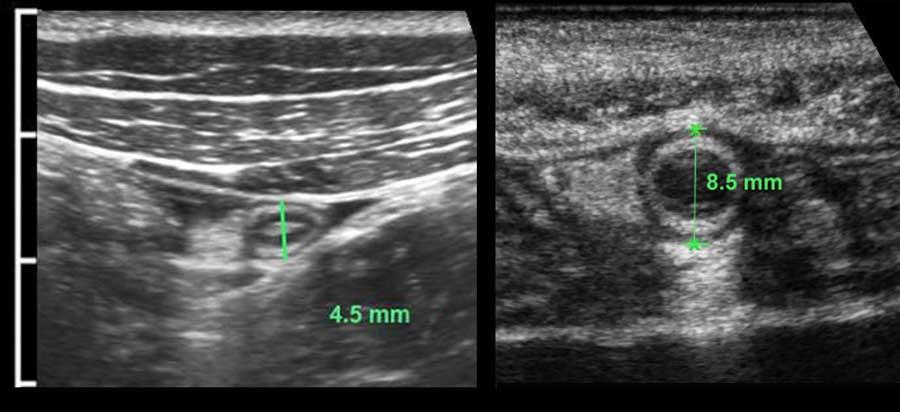

Đường kính ngoài của ruột thừa được đo theo cách tương tự như ruột: trong quá trình ép vừa phải từ bờ ngoài của lớp cơ thành bụng trước đến bờ ngoài của lớp cơ thành bụng sau.

Được đo như vậy, đường kính của ruột thừa bình thường này (trái) là 4,5 mm và của ruột thừa viêm này (phải) là 8,5 mm.

Trong nhiều sách giáo khoa, giá trị ngưỡng cắt được báo cáo là 6 mm, tuy nhiên đây không phải là giá trị đáng tin cậy.

Rettenbacher (Radiology 2001; 218: 757-62) đã thực hiện một nghiên cứu lớn và phát hiện rằng đường kính của ruột thừa bình thường từ 6 mm trở lên chiếm 27% các trường hợp, với khoảng dao động từ 2-13 mm.